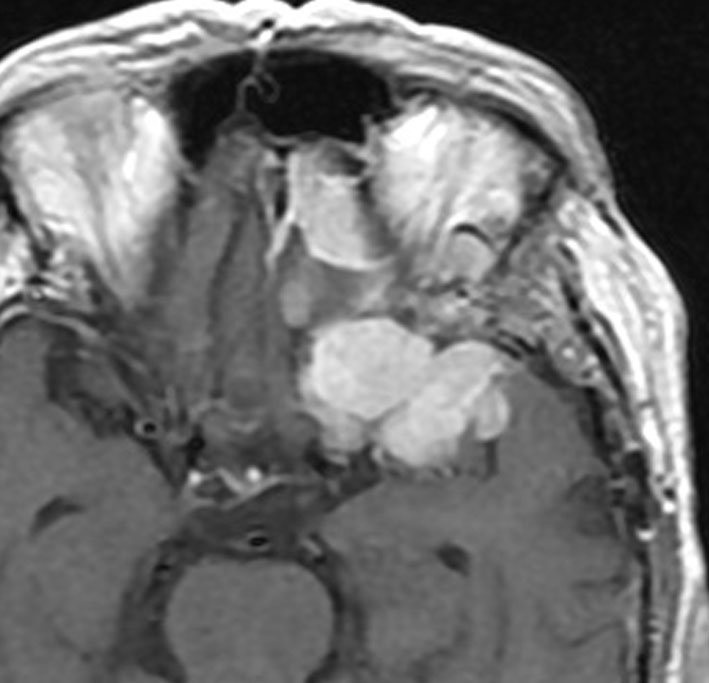

もともと巨大な傍矢状洞 非定型髄膜腫 WHO grade 2で全摘出しました。左側は8年後の再発で摘出。中央は9年後の再発で摘出。右側は11年度の再発で側頭穹窿部にも転移しています。

左は13年後の前頭先端部再発。中央は15年後の蝶形骨縁再発。右は17年後の前頭蓋底と蝶形骨縁再発です。その都度,摘出しています。

18年後には中頭蓋底から蝶形骨洞方向へと浸潤して大きな再発となりました。悪性度が高くなると頭蓋内の至る所へ転移再発します。

このような髄膜腫は放射線治療にも抵抗性で,摘出と放射線外科治療を何度もなんども繰り返している内に制御がきかなくなります。

病理像です。左側は初発時のグレード2の髄膜腫。右側は遠隔転移をするようになった頃のものです。グレード2という病理診断でしたが,ほぼグレード3です。核異型性が高く,分裂像が散見され壊死を伴います。MIB-1標識率は25%に達しました。肉腫ともいえるものです。